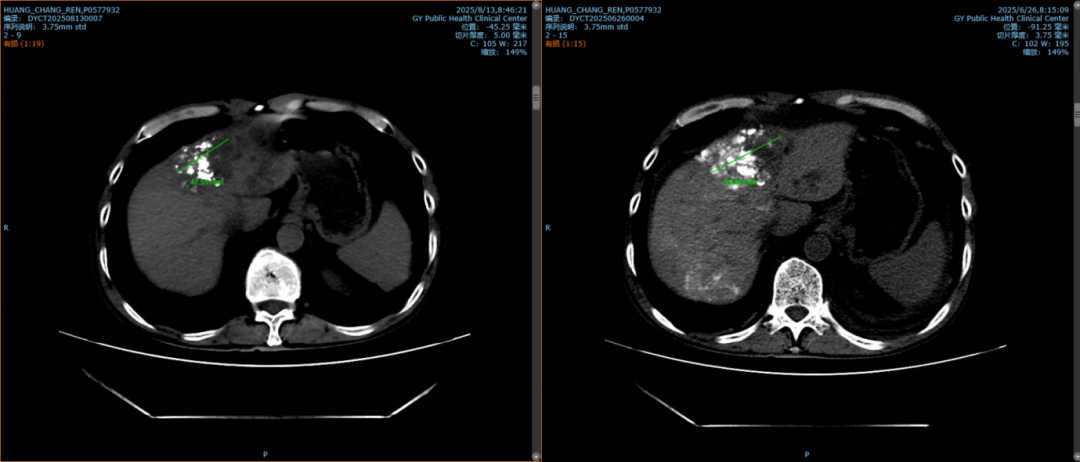

圖2:患者病灶最大層面,右側(cè)為第一次TACE術(shù)后病灶直徑約9cm,左側(cè)為此次HAIC術(shù)后病灶縮小至8cm。